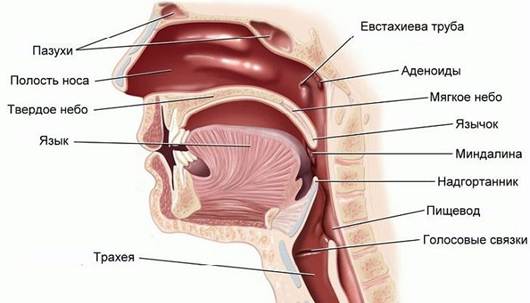

Сначала кажется, что дело только в кривых зубах и нехватке места, но дальше начинается каскад проблем: зубы стираются, нижняя челюсть развивается неправильно. Но самое главное — страдает носовое дыхание, а значит, ухудшается снабжение мозга кислородом.

Главная — нарушение носового дыхания. Аденоиды или хроническая аллергия заставляют ребёнка дышать ртом. Чтобы воздух проходил, он инстинктивно опускает язык на дно полости рта. А ведь в норме язык должен лежать на нёбе. Когда он там лежит, он как бы распластывается по нёбу, постоянно на него давит и естественным образом его расширяет. Если язык всё время внизу, то этого не происходит, и челюсть остаётся узкой.